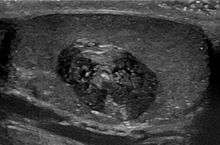

Epidermoid cyst in a testicle - ultrasound

Epidermoid cysts are usually diagnosed when a person notices a bump on their skin and seeks medical attention. The definitive diagnosis is made after excision by a pathologist based on microscopic appearance of a cystic lesion lined by cornified epithelium containing lamellated keratin without calcifications. They can also be seen as isointense lesions on MRI or hyperintensities on FLAIR.